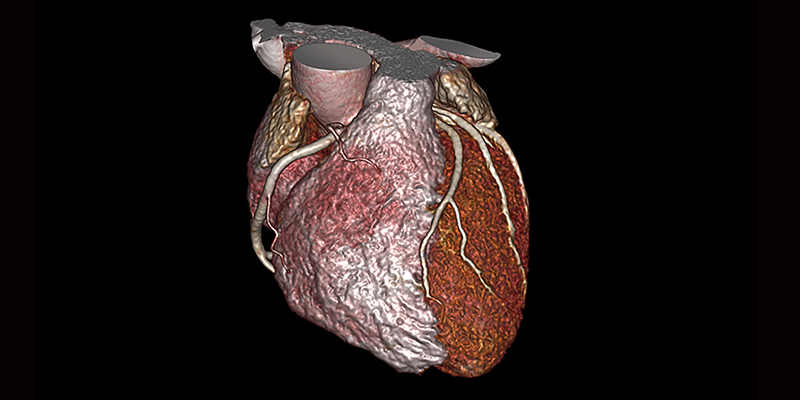

КАРДІОЛОГІЧНІ ПАКЕТИ